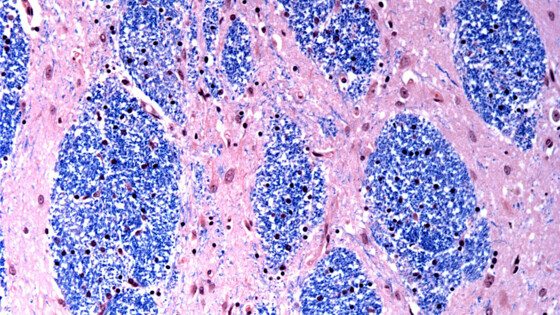

В новом исследовании ученые изучили мозговую ткань, пожертвованную 53 пациентами с болезнью Гентингтона, и 50 здоровыми людьми.

Специалисты сосредоточились на мутации Гентингтона, которая включает в себя участок ДНК в определенном гене, где трехбуквенная последовательность — CAG — повторяется по крайней мере 40 раз.

У людей без этого заболевания эта последовательность повторяется всего от 15 до 35 раз. Ученые обнаружили, что тракты ДНК с 40 или более такими «повторами» со временем расширяются, пока не станут длиной в сотни CAG. Как только CAG достигают порогового значения около 150, определенные типы нейронов начинают отмирать.